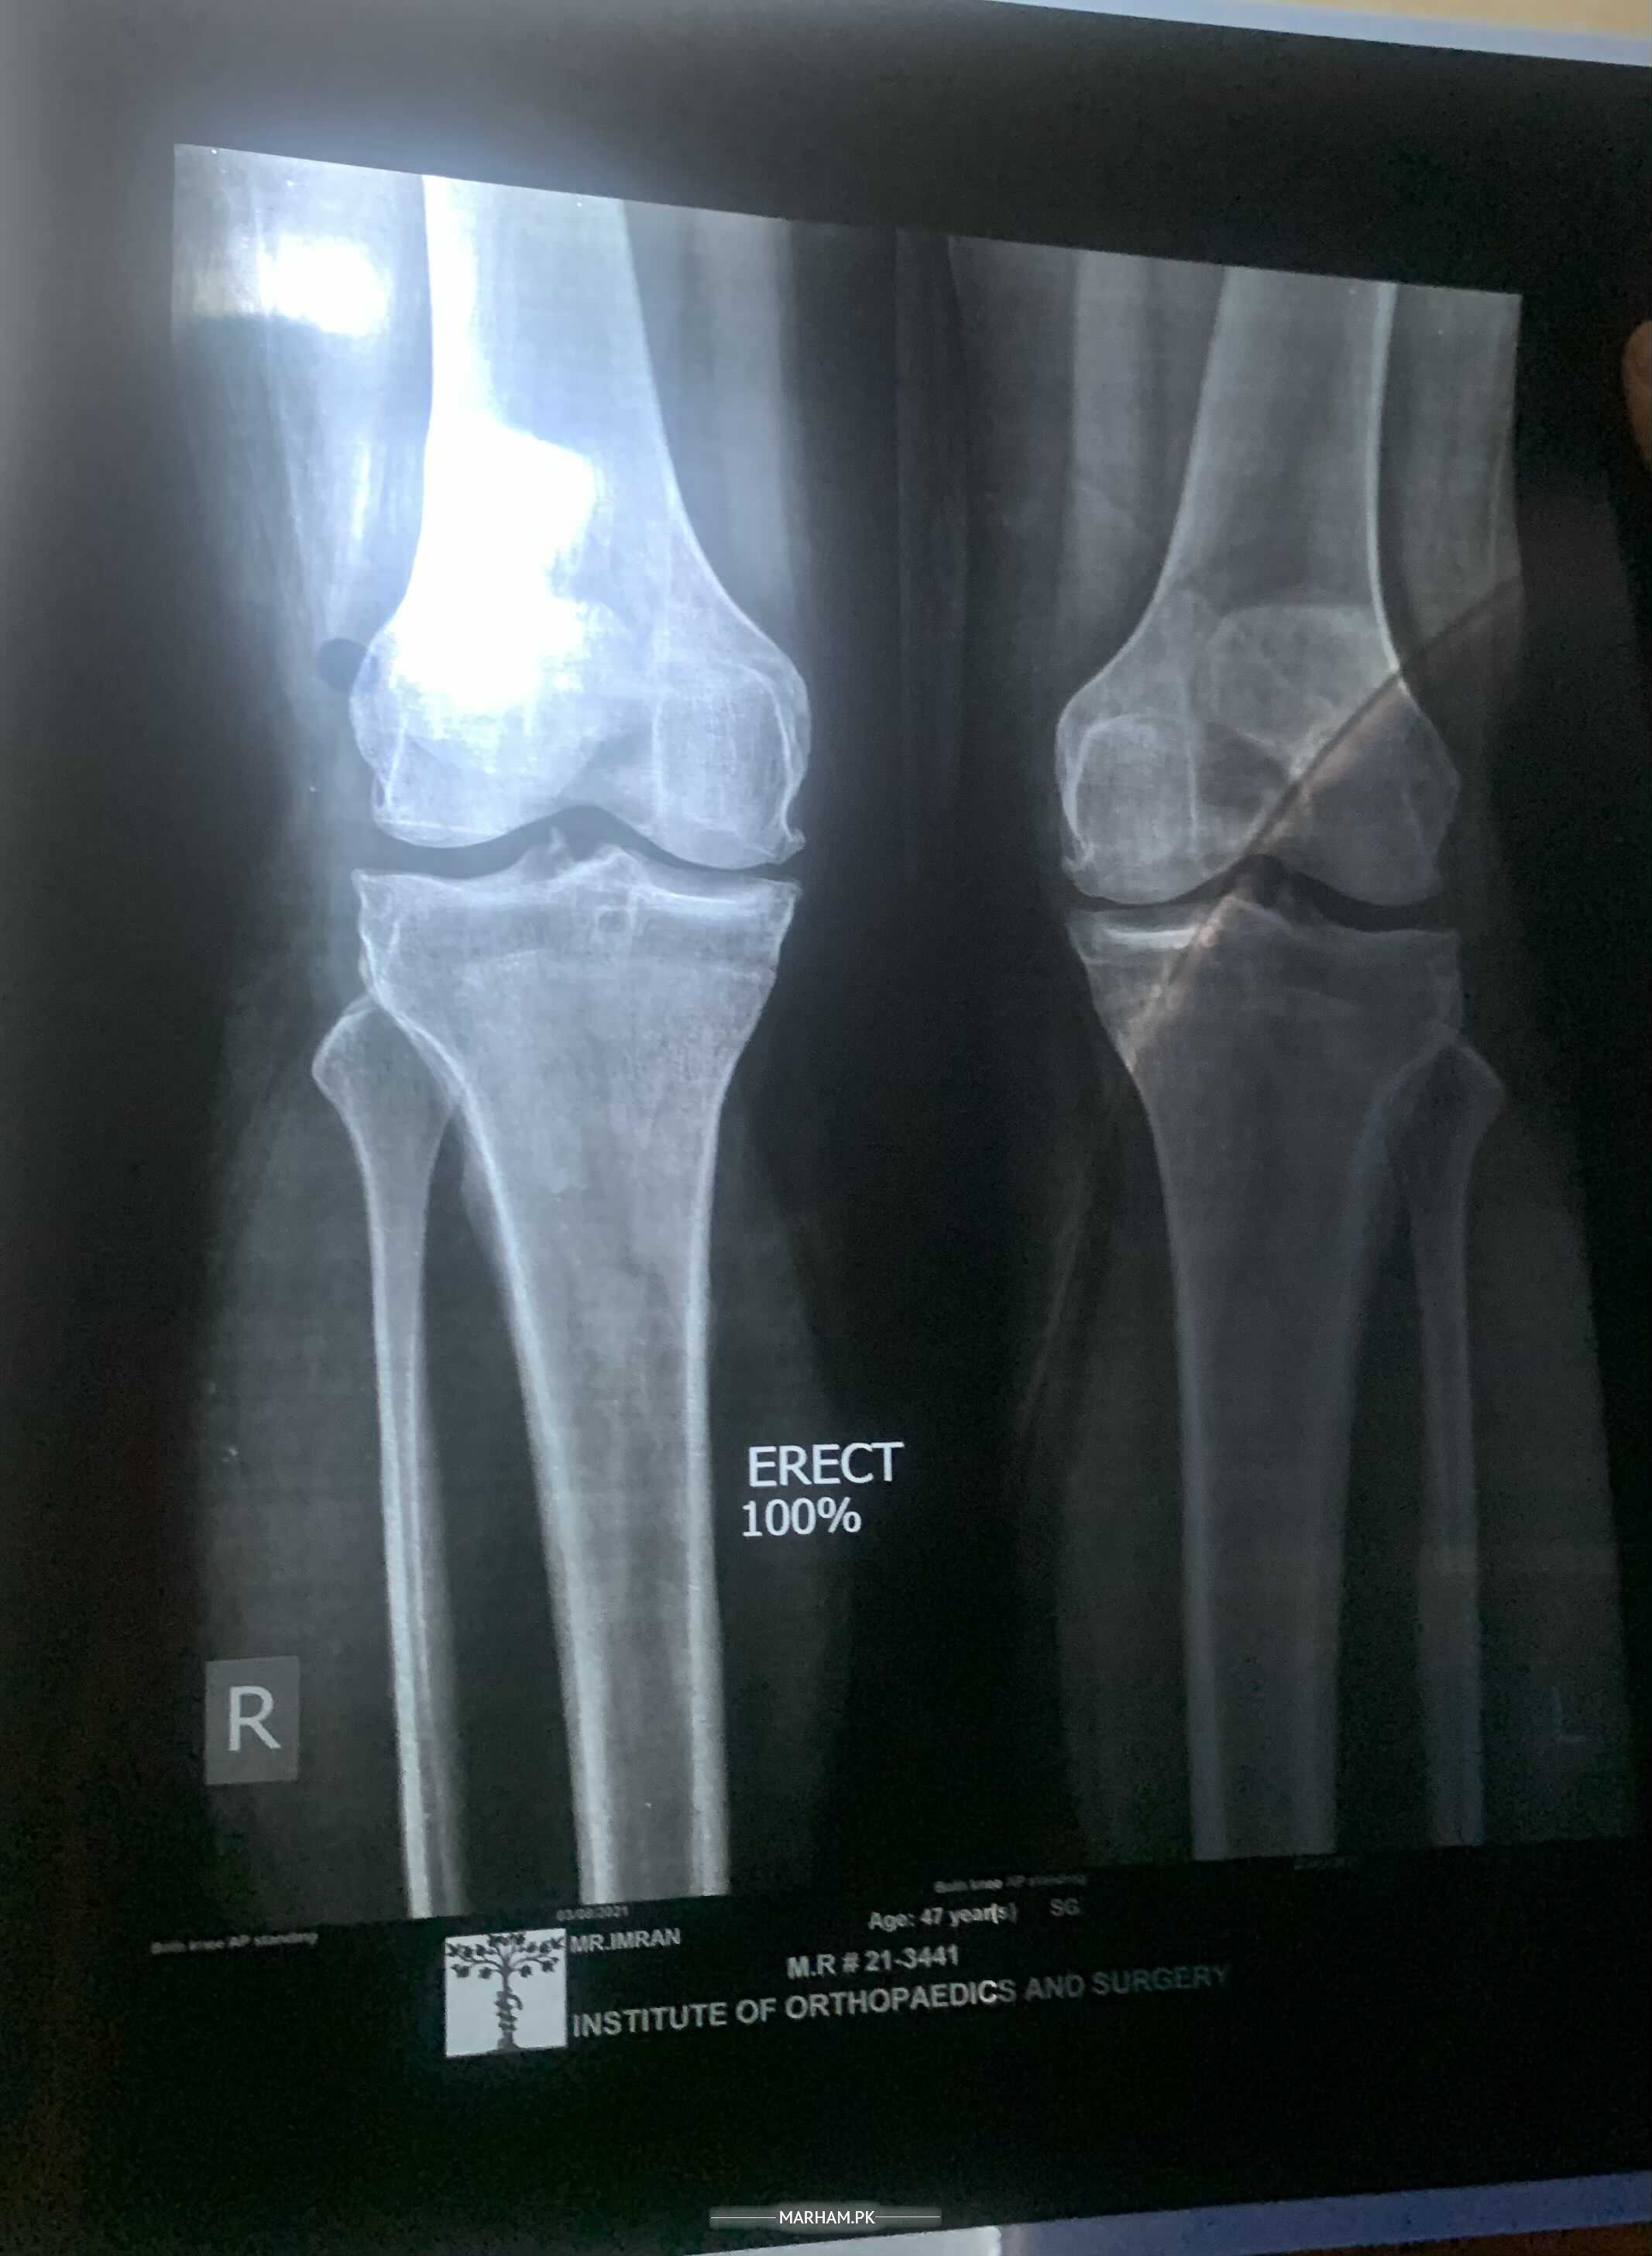

Suffering from osteoarthritis diagnosed 3 years ago, Dr said it is on 2nd stage. Now cannot fold the knee. Any possibility of getting rid of this disease?

X ray plz

?????????? ?????????? ?????????? ????? ????????????? X-ray uploaded

X-ray uploaded

Osteoarthritis is not reversible but can control its symptoms by the following.1) loose weight 2) start doing quadriceps muscle strengthening exercises isometric ones with weight 3) avoid joint loading activities like stairs climbing, walking on uneven surfaces, jumping , running, walking is ok. Physical therapy and some pain medications.

Hi, osteoarthritis by definition is progressive disease. keep walking and exercise and painkillers as required. once it gets very bad the definite cure is total knee replacement. Thanks